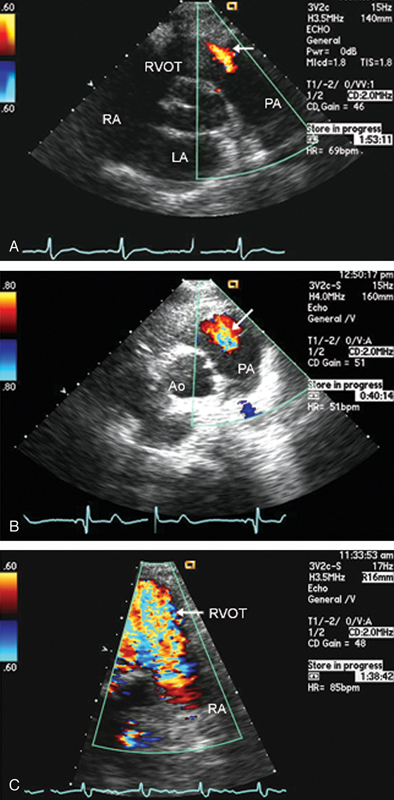

فحوصات تشخيصية لبعض امراض القلب والشرايين التاجية